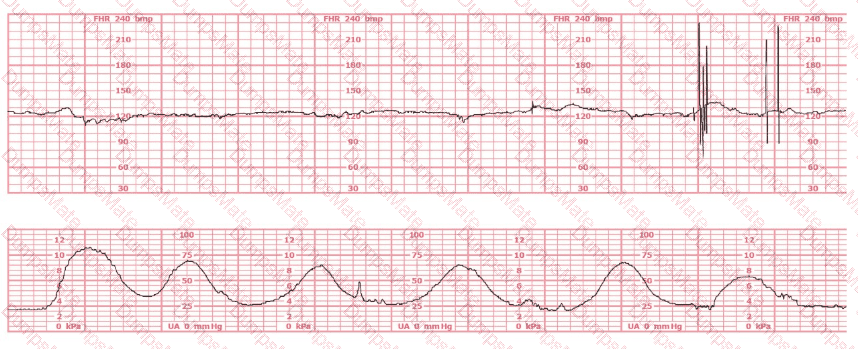

A woman at 41-weeks gestation is being induced. She is 2 cm dilated and is on oxytocin at 8 milliunits/minute. Based on the fetal heart rate tracing shown, the best initial response is to:

EFM Question 9